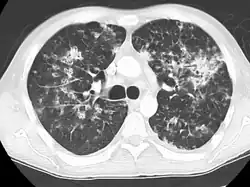

A case of miliary tuberculosis in an 82-year-old woman:

-

X-ray, 13 days after onset, showing bilateral interstitial infiltrates -

CT, 16 days after onset, showing extensive pulmonary parenchymal involvement consisting of irregular septal thickenings with ground-glass areas and centrilobular nodules with a peri-lymphatic distribution -